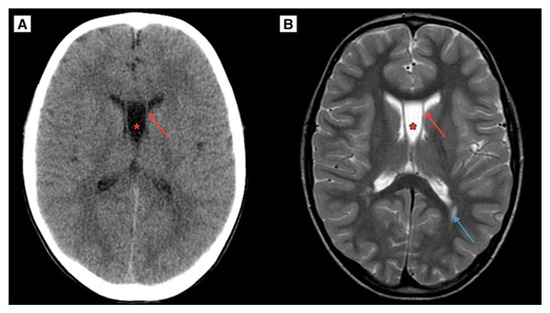

The patient had a CT scan of the brain 12 years ago at the time of a head trauma, which showed no evidence of ventricular enlargement, intracranial cysts, hydrocephalus, or any symptoms. CT brain scan imaging revealed a CSP and CV developmental variant (Figure 4), providing a unique example of evaluating the progression of CSP and CV growth in dynamics. Additionally, an MRI scan of the brain was performed 12 years ago, demonstrating an exceptional case of CSP and CV cyst dynamic progression (Figure 4). Notably, linear lesion-like changes along the posterior parts of the lateral ventricles were observed, which may indicate a possible past mild perinatal injury. In this case, such an injury could represent one of the rarely described potential etiological factors contributing to the development of a CSP cyst over the patient’s lifetime.

Figure 4.

(A) A CT scan of the brain in the axial plane, performed on an 8 year-old Caucasian male (2011) demonstrated the developmental variant of CSP and CV, with a maximum diameter of approximately 12.2 mm. (B) The same patient’s MRI scan of the brain T2W axial sequence demonstrated a CSP and CV developmental variant. Notably, Blue arrow—linear lesion-like focal changes along the posterior parts of the lateral ventricles, which could be caused by previous mild perinatal injury. Red arrow—septum pellucidum wall, Red asterisk—CSP and CV.